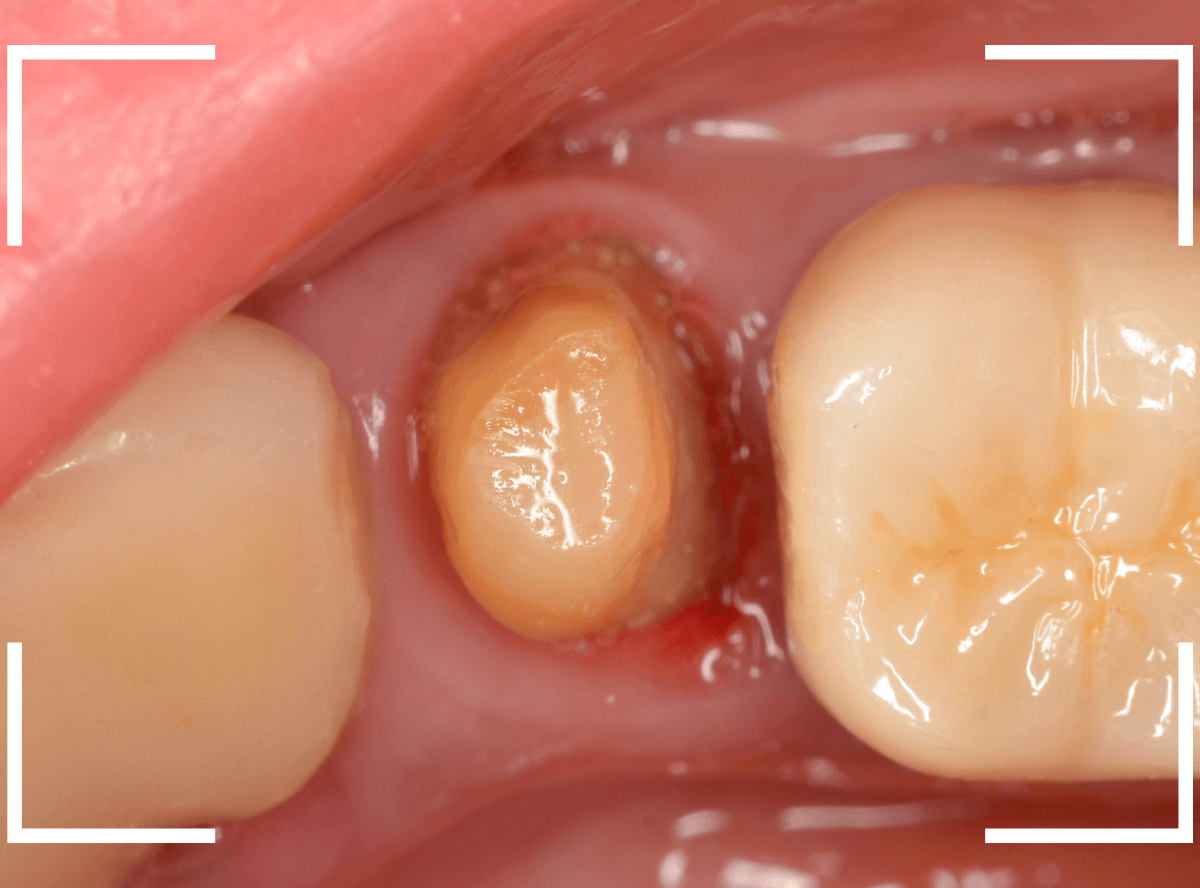

今回は、歯肉の中まで歯が欠損しているので、このまま土台とさし歯を作り直しても、いい結果にはなりません。

患者さんに状況を説明し、歯の周りの歯肉を麻酔をして電気メスでトリミングします。

このように歯の際が歯肉からしっかり出てる状況で製作しないと、さし歯はしっかりお口の中で安定しません。

この状態で新しい土台(ファイバー・コア)の型を取ります。